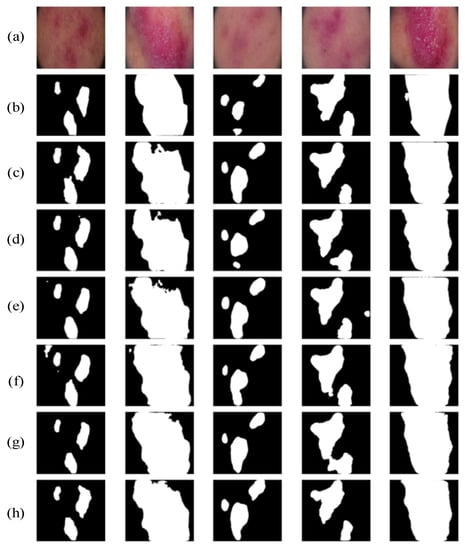

4.5.3. Private Dataset Experiments